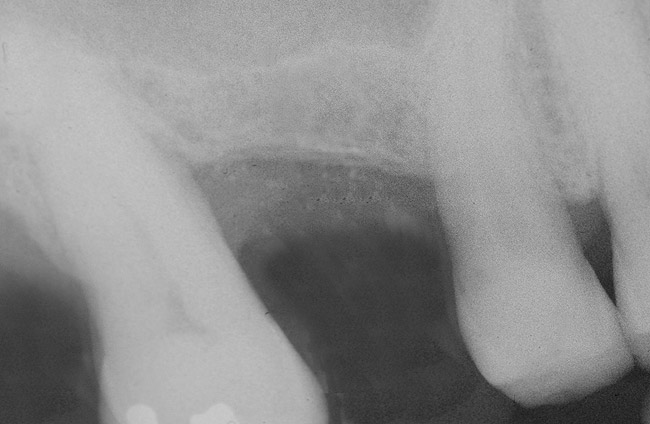

First, a periapical radiograph is taken to determine the amount of bone subantrally. It should be noted that a periapical film has an average error of 14%.23 Therefore, it is advantageous to take the radiograph in a manner that includes a marker (5-mm wide ball bearing) in order to be able to calculate the magnitude of radiographic error (Figure 1).

Figure 1  At tooth site No. 14, a periapical radiograph was taken with the long-cone paralleling technique. The radiographic ball marker measured 5.8 mm while its actual diameter is 5 mm. The enlargement is 0.8 mm, therefore the magnification error is 0.8/5 = 16%. By correcting for this error, a closer approximation of the amount of bone from the osseous crest to the sinus floor can be made.

Figure 1